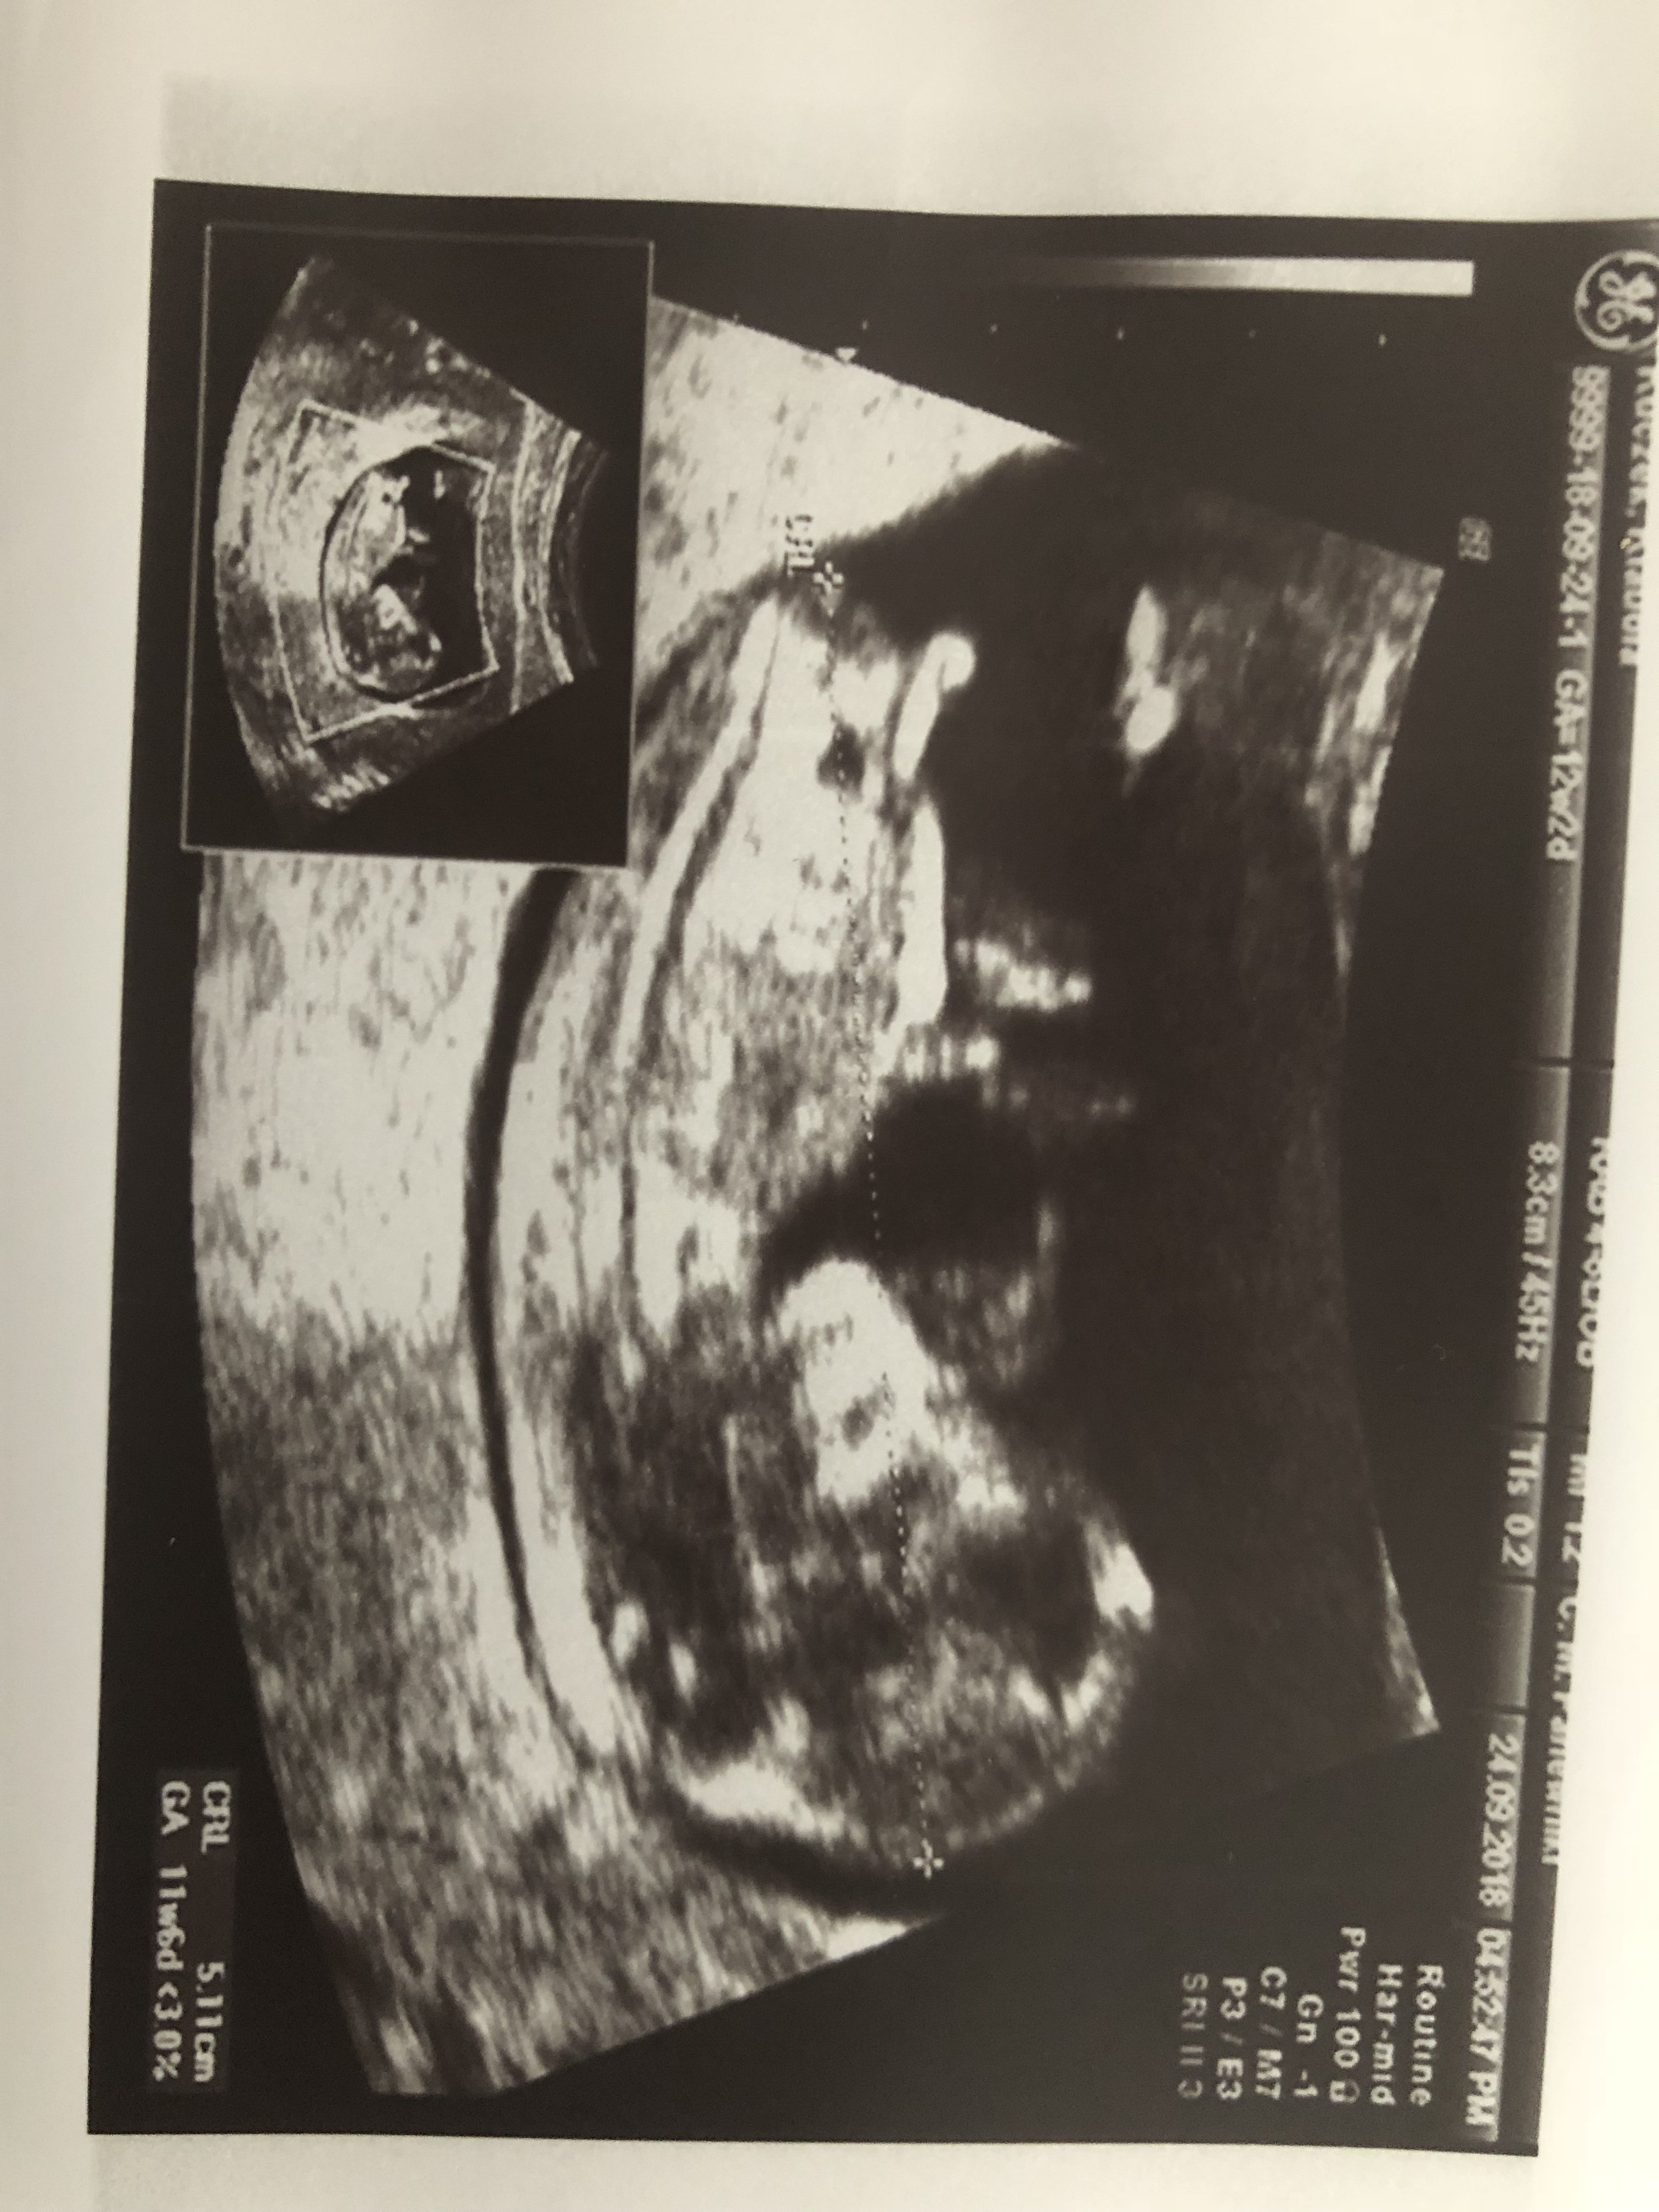

Witam Was. Może po tych zdjęciach da się odczytać płeć dzidziusia? Dodam że jest to 12+4 tc na prenatalnych Pani dr nie była pewna zajrzała tylko między nóżki na wyrostek nie patrzyła.

Załączniki

• DSC_2504.JPG

DSC_2504.JPG

1,9 MB · Wyświetleń: 408

• DSC_2503.JPG

DSC_2503.JPG

1,9 MB · Wyświetleń: 412

• DSC_2505.JPG

DSC_2505.JPG

1,7 MB · Wyświetleń: 398

Sysia obstawialabym chlopaka na potty shot cos odstaje..mojej corce w tym tyg ciazy nic nie odstawalo.

Klaudia przykro mi ale na Twoich zdjeciach nie widze nuba.